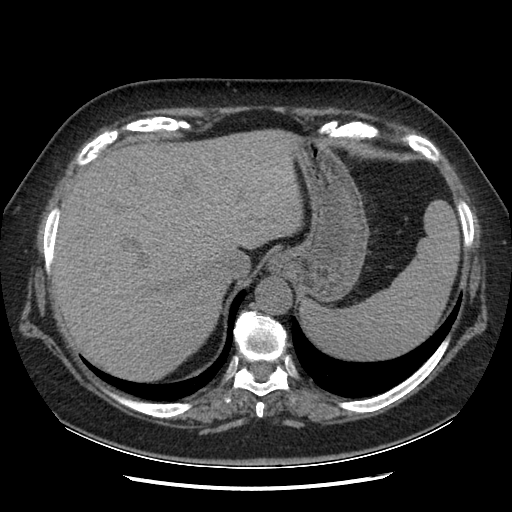

Original VENOUS CT scan

Full window (WL 1023.5, WW 4095 β†’ Low βˆ’1024, High +3071)

Actual HU range: [-1024.0, 1086.0]